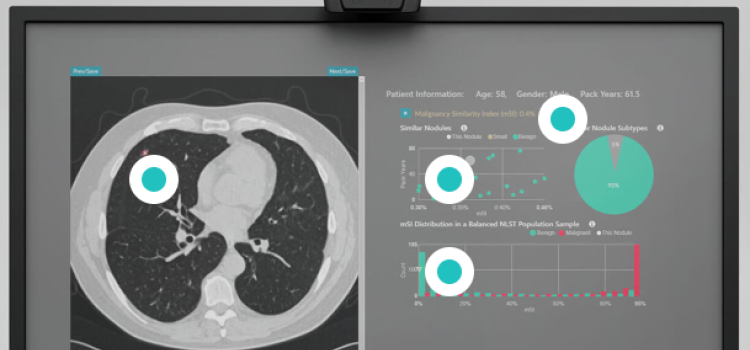

Nov. 3, 2025 — RevealDx, a leader in the characterization of lung nodules, has introduced MDR Certification of RevealAI ...